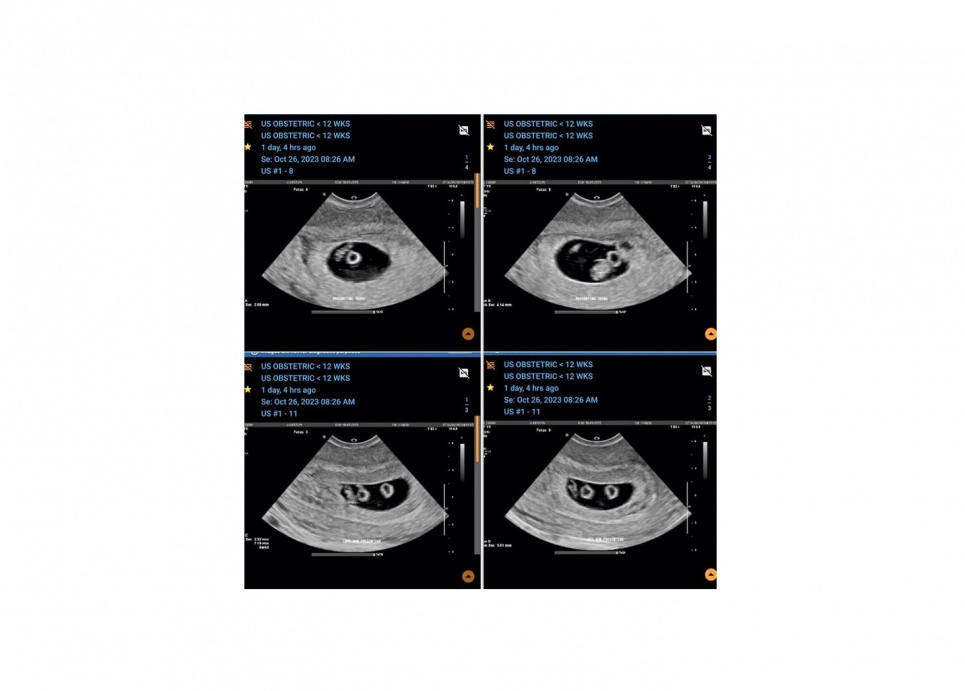

23-летняя австралийка Эбони Эппс беременна сразу двумя парами однояйцевых близнецов. Роды путем кесарева сечения запланированы на апрель. Медики поражены таким редким случаем, который случается один раз в 70 миллионов беременностей. Об этом сообщает The New York Post.

Молодой паре сначала сказали, что они ожидают двойню во время первого сканирования в сентябре прошлого года. Однако через месяц врачи обнаружили, что в каждом из мешков было по два младенца, а это означает, что Эппс беременна двумя наборами идентичных близнецов.